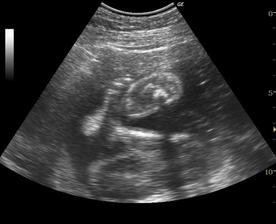

Naša maličká Emka alebo Silvinka...🙂

Od 19. júna 2008, teda od 21. týždňa vieme, že sa nám na 99% narodí dievčatko...na mene neodznela ešte úplná zhoda, preto Ema alebo Silvia...no ja dúfam, že sa mi podarí presadiť Emu, aj keď Silvia je tiež krásne meno...🙂...

a dnes, 16.10.2008, teda v 38. týždni, padlo definitívne rozhodnutie o mene...skôr moje rozhodnutie ako tatkove...🙂...takže naša prvorodená dcérka sa bude volať Ema Silvia...🙂